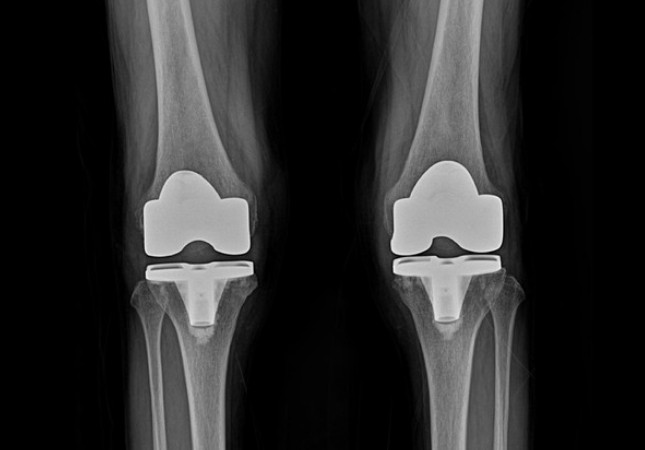

퇴행성 관절염 말기증상

퇴행성 관절염 말기에는 관절의 강직이 생겨 무릎이 다 펴지지 않거나 무릎을 구부릴 때 제한이 생길 수 있고 걸을 때 통증이 매우 심해지고 다리를 움직이지 않는 밤에도 통증이 심해 잠을 설치는 경우도 있습니다. 연골이 완전히 닳아 없어진 말기에는 인공관절수술을 해야 하는데, 인공관절수술은 말 그대로 인공으로 만든 관절을 끼워 넣는 수술로 손상된 연골 부분을 제거하고 그 위에 인공 관절을 삽입하는 수술입니다.